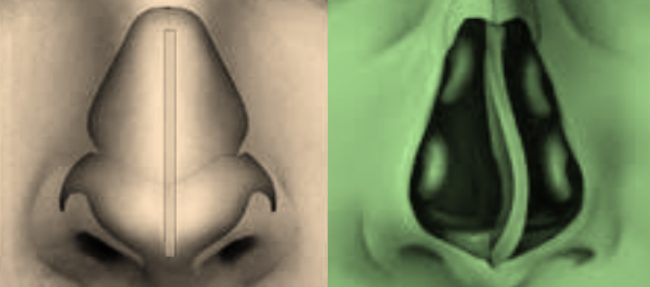

Структуры пазух носа, также называемые придаточными пазухами носа, представляют собой 4 пары воздушных пространств, расположенных внутри лицевых костей, и каждая названа в честь костных структур, в которых они расположены (верхнечелюстная, решётчатая, лобная и клиновидная пазухи). Пазухи, которые частично присутствуют при рождении, почти полностью развиваются примерно к 12-14 годам. Он имеет такие функции, как увлажнение вдыхаемого…